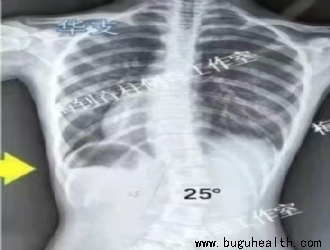

- 据统计,目前我国脊柱侧弯患者超300万,并以每年30万的速度递增,其中超过半数为青少年。脊柱侧弯成为继肥胖症、近视之后,我国儿童青少年健康的第三大“杀手”。.....

- 据统计,目前我国脊柱侧弯患者超300万,并以每年30万的速度递增,其中超过半数为青少年。脊柱侧弯成为继肥胖症、近视之后,我国儿童青少年健康的第三大“杀手”。要知道,脊柱侧弯不仅影响体型,更重要的是会导致严重的身体健康问题。 .....

- 有大约80%脊柱侧弯的发病原因还没有得到确定,因为它是由很多因素引起的。青少年的脊柱侧弯大部分是特发性脊柱侧凸,可能会和遗传、神经系统异常、骨骼生长异常、激素和代谢功能障碍、生物力学因素等有关,还可能与环境及生活方式等有关。.....

- 脊柱侧弯,顾名思义是指脊柱的侧向弯曲,同时会伴有胸部的扭曲、椎体的旋转。引起脊柱侧弯的原因有很多,包括遗传倾向,激素影响,脊椎与脊髓生长不协调,引起脊柱不对称生长和中枢神经系统的改变皆有可能,但并不足以充分解释发病原因。因此,大部分脊柱侧弯成因并不明确,故称为特发性脊柱侧弯,而一般在青少年时期(约1.....